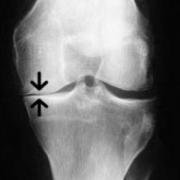

Unloading protects the vulnerable joint cartilage on that side of the knee joint. Once unloaded, the collapsed joint space should open up as weight is taken on that side.